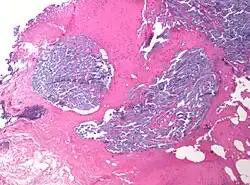

A desmoplastic response is characterized by larger stromal cells with increased extracellular fibers and immunohistochemically by transformation of fibroblastic-type cells to a myofibroblastic phenotype.[2] Myofibroblastic cells in tumors are differentiated from fibroblasts for their positive staining of smooth-muscle actin (SMA).[2] Furthermore, an increase in total fibrillar collagens, fibronectins, proteoglycans, and tenascin C are distinctive of the desmoplastic stromal response in several forms of cancer.[14] Expression of tenascin C by breast cancer cells has been demonstrated to allow for metastasis to the lungs and cause the expression of tenascin C by the surrounding tumor stromal cells.[15] In addition, tenascin C is found extensively in pancreatic tumor desmoplasia as well.[16]

While scars are associated with the desmoplastic response of various cancers, not all scars are associated with malignant neoplasms.[3] Mature scars are usually thick, collagenous bundles arranged horizontally with paucicellularity, vertical blood vessels, and no appendages.[3] This is distinguished from desmoplasia in the organization of the tissue, the appendages, and orientation of blood vessels. Immature scars are more difficult to distinguish due to their neoplastic origins.[3] These scars are hypercellular with fibroblasts, myofibroblasts, and some immune cells present.[3] The immature scars can be distinguished from desmoplasia by immunohistochemical staining of biopsied tumors that will reveal the type and organization of cells present as well as whether recent trauma has occurred to the tissue.[17]